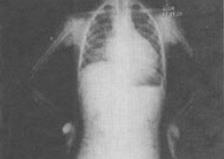

3、 患者男,8岁,易疲劳,活动后心悸、气急,结合X线检查,最可能的诊断是()。

- A、房间隔缺损

- B、室间隔缺损

- C、肺动脉狭窄

- D、动脉导管未闭

- E、法洛四联症

【正确答案-参考解析】:参加考试可见 点击进入查看